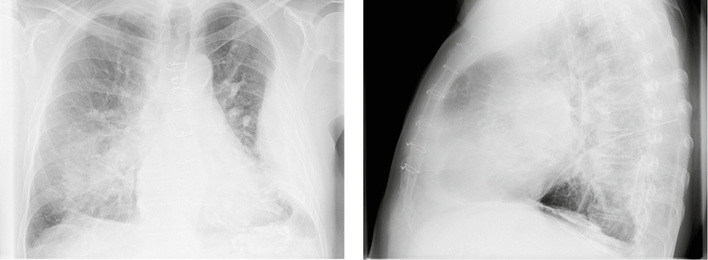

Abb. 1a,b:

Röntgen-Thorax in 2 Ebenen vom 16.01.2017

Kasuistik: Asbestpleuritis

Falldarstellung  Asbestbedingte Erkrankungen der Pleura werden häufig nicht oder nicht rechtzeitig erkannt. Sie manifestieren sich in Form von Schwielen und/oder Verkalkungen entweder der viszeralen oder der parietalen Pleura. Nicht selten tritt als Erstsymptom ein einseitiger Pleuraerguss auf. Ein solcher Fall wird hier dargestellt. Heike Berlinghof, Thomas Nauert